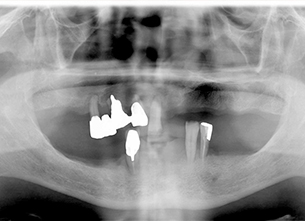

症例1 : 上下顎無菌顎症例

69歳、男性。

• 上顎は両側サイナスリフトと同時に即時荷重を行った。

• 下顎は抜歯即時埋入即時荷重を行った。

• 最終補綴物は、チタンのP.I.B.とM.B.のコンビネーションで修復した。

• 本症例の要旨は第39回日本口腔インプラント学会(大阪)にて症例報告した。